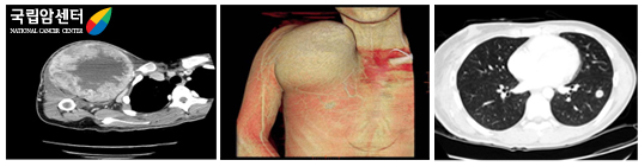

종양의 폐전이 유무를 판단하거나 복부 장기로의 전이 등 종양의 병기(stage) 결정에 유용하게 이용되고 있으며, 원발암의 추적 조사 등에도 이용되고 있습니다. 3차원 혈관조영 전산화단층촬영(CT)은 수술 전 종양의 혈관분포도와 종양의 입체를 정확히 확인하는데 도움이 됩니다.

[ 오른쪽 견관절 주위 육종의 전산화단층촬영, 같은 환자의 좌측 폐전이 CT ]

연부조직종양을 판단하는 데 탁월한 검사입니다. 특히 종양의 병기(stage)를 결정하는 데 필수적인 검사로 종양과 주위 조직 특히, 혈관 및 신경과의 상관관계를 파악하는 데 중요한 검사입니다. 또한 종양에 대한 항암화학요법 전후에 영상을 비교하여 치료 효과 판정에 이용하기도 합니다. MR 분광기(spectroscopy)의 사용으로 종양실질의 구성 성분을 예측할 수 있어 진단에 도움을 줍니다.